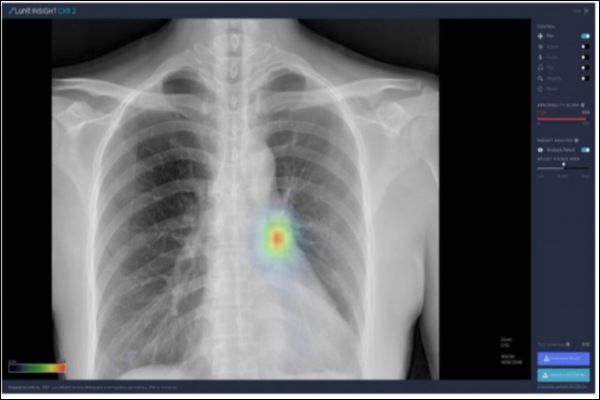

▲루닛의 폐 질환 진단 소프트웨어 ‘루닛 인사이트 CXR’로 흉부에 비정상 소견을 표시할 수 있다.[사진=루닛]

이번 국방부가 제공한 흉부 엑스레이 영상 데이터 2만 건을 대상으로 한 연구에서 루닛의 인공지능은 활동성 폐결핵을 정확히 진단해냈다. 특히, 엑스레이 한 장 당 소요된 판독 시간이 수 초에 불과해, 인공지능을 활용할 경우 감염성 질환에 대한 대규모 선별검사에서 보다 정확하고 신속한 군 의료체계 수립 가능성을 보여줬다.